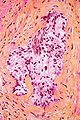

Perineural invasion in prostate carcinoma. H&E stain.

Perineural invasion, also known as perineural tumour, is the presence of a tumour within the nerve sheath. It is abbreviated as PNI.

• Tumour within the nerve sheath.